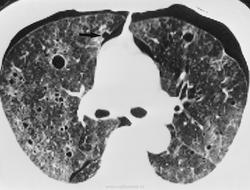

Онкология. ОГК. Полостные (кавитирующие) метастазы. "Атипичные" метастазы. +

"Полостные" метастазы

Множественные метастазы.